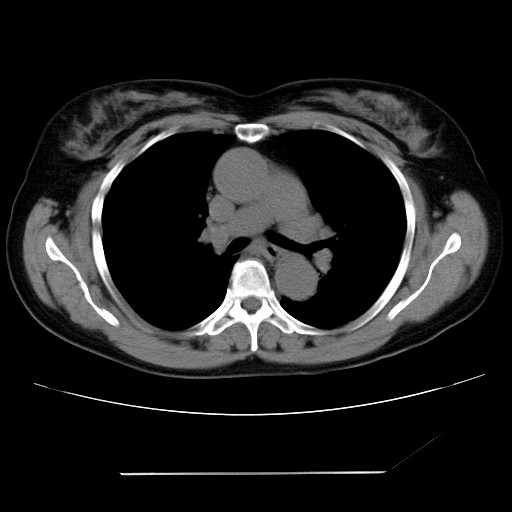

女性,62岁,长期咳嗽,既往从事工作有粉尘接触,有高血压病史,110/150mmhg,近日咳嗽加重,脸面浮肿,请大家帮看下,

1、尘肺;2、慢性支气管炎合并肺部感染;3、心影增大(左房、左室大),考虑高血压性心脏病。

慢支并肺部炎症;右肺结核球?主肺动脉、右肺动脉影不宽,右心室不大,不支持肺心病;无心包积液。

间质性肺炎,有纤维化趋势。

1)慢性支气管炎并肺部感染、肺气肿。2)肺间质纤维化。

间质性肺炎,左下肺机化性肺炎。